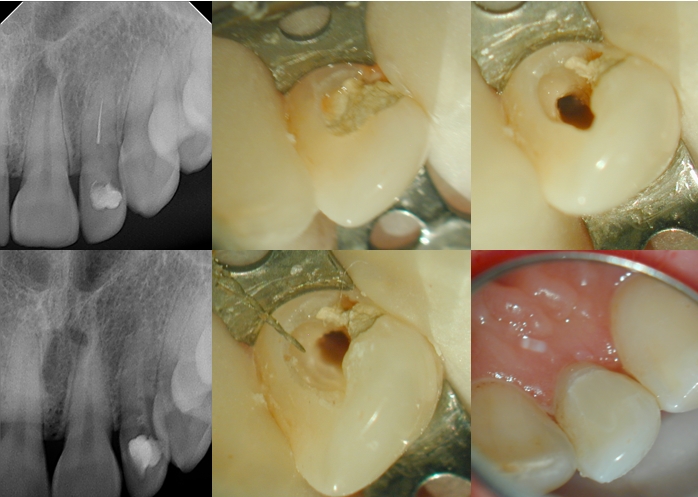

This patient was seen by a dentist friend of mine. During the final shape, she separated a rotary instrument. Patient can not afford endodontist fees and is on Medi-Cal. My friend asked if the instrument should be removed or can be left in there as she was able to bypass it. I said, “I should be able to remove it, without too much damage to the tooth”. She said, she (my friend) would pay for it and not to charge the patient. I saw the patient, who was worried that she was going to lose her tooth. I extended the access facially, and was able to take out the instrument with minimal effort by braiding three files around it. Calcium hydroxide, temporary composite restoration as a temporary and sent the patient back to her GP. Of course I won’t charge my friend, but will give her some pointers about SLA, and let her know that this is a one time favor!